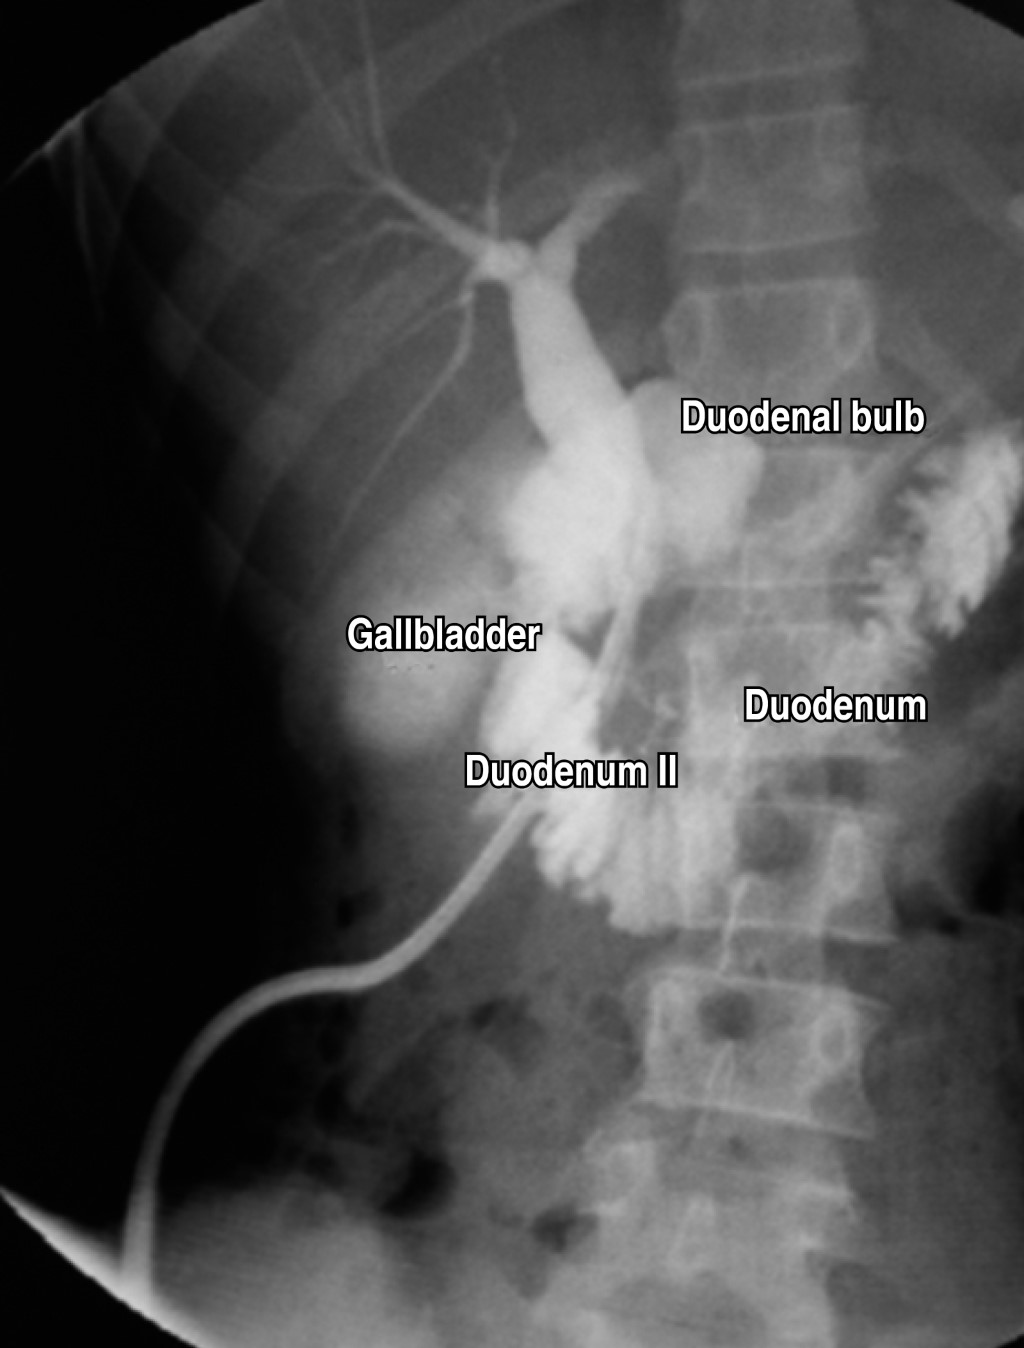

The patient underwent exploratory laparotomy where a tumor mass of approximately 6 × 8 cm was identified at the level of the head of the pancreas attached to the second portion of the duodenum, so we proceeded to perform enucleation by dissection of the second portion of the duodenum and the trans-pancreatic portion involving the main pancreatic duct, The duodenum was then splinted with a No. 12 Nelaton, which was exteriorized through the second portion of the duodenum towards the abdominal wall at the height of the right flank, and fixed with a PDX 3 (polydioxanone) suture (Figures 2, 3 and 4).

The patient had a favorable postoperative period of 33 days. Additional to general measures, broad-spectrum antibiotic therapy was administered corresponding to amikacin 680 mg intravenous every day for 10 days accompanied by imipenem 500 mg every six hours intravenous for 15 days, and then cefalexin 500 mg orally every eight hours for seven days. After discharge, cefuroxime 500 mg orally every 12 hours for five days were given. Total parenteral nutrition was started on the third postoperative day and maintained for 10 days. On the seventh postoperative day, a strict liquid diet was started which was then progressed to a soft diet that was well tolerated. A somatostatin analogue from the beginning of the postoperative period at a rate of 4 µg intravenous every eight hours until discharge was used. A rigorous control of the drain was established, performing daily clamping of the drain for 24 hours and then continuing with control of the fistula to see if there was any fluid arrest or leakage Finally, it was decided to remove the drain (Figure 5).